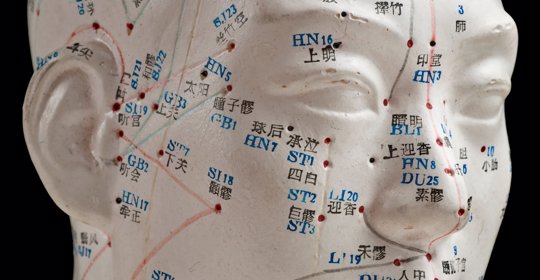

前額頭痛:按壓百會、印堂、風池、頭維